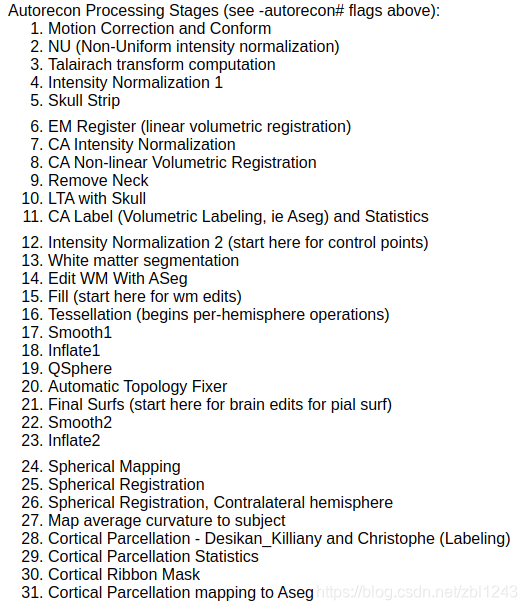

有以下处理过程: